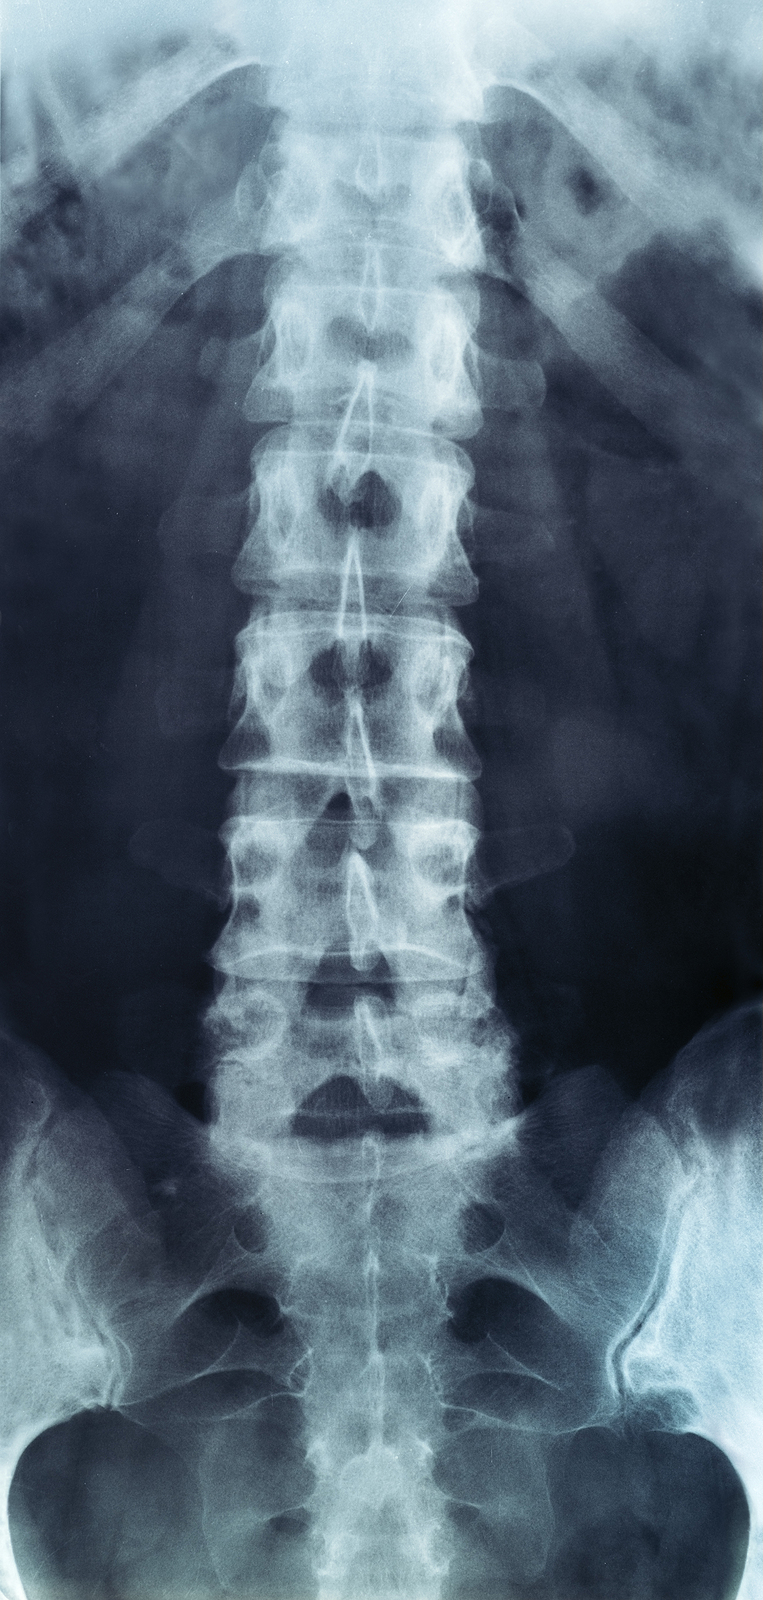

X-rays

X-rays are usually the first test ordered before any of the more specialized tests are completed. X-rays use electromagnetic radiation to show problems with bones and can also reveal problems such as fractures, infections, or bone tumors. X-rays of the spine can give your doctor information about bone alignment and can demonstrate how much degeneration has occurred in the spine. Both alignment and degeneration can affect the amount of space in the neural foramina and between the discs, which subsequently impacts the nerves in the area. This is important information your health care professional can use to establish a treatment plan.

Flexion and Extension X-rays

Special x-rays called flexion and extension x-rays may help to determine if there is true instability between vertebrae. These x-rays are taken from the side as you bend as far forward and then as far backward as you can. Comparing the two x-rays allows the doctor to see how much motion occurs between each spinal segment.